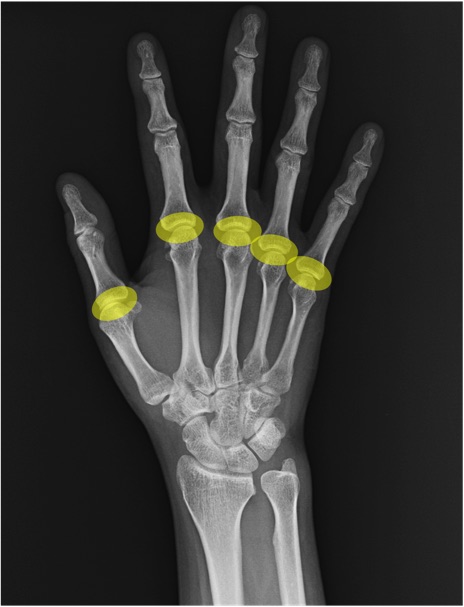

MP関節(metacarpophalangeal joint)の手関節レントゲン画像における正常解剖

中手骨(metacarpal bone)

基節骨(proximal phalanx)